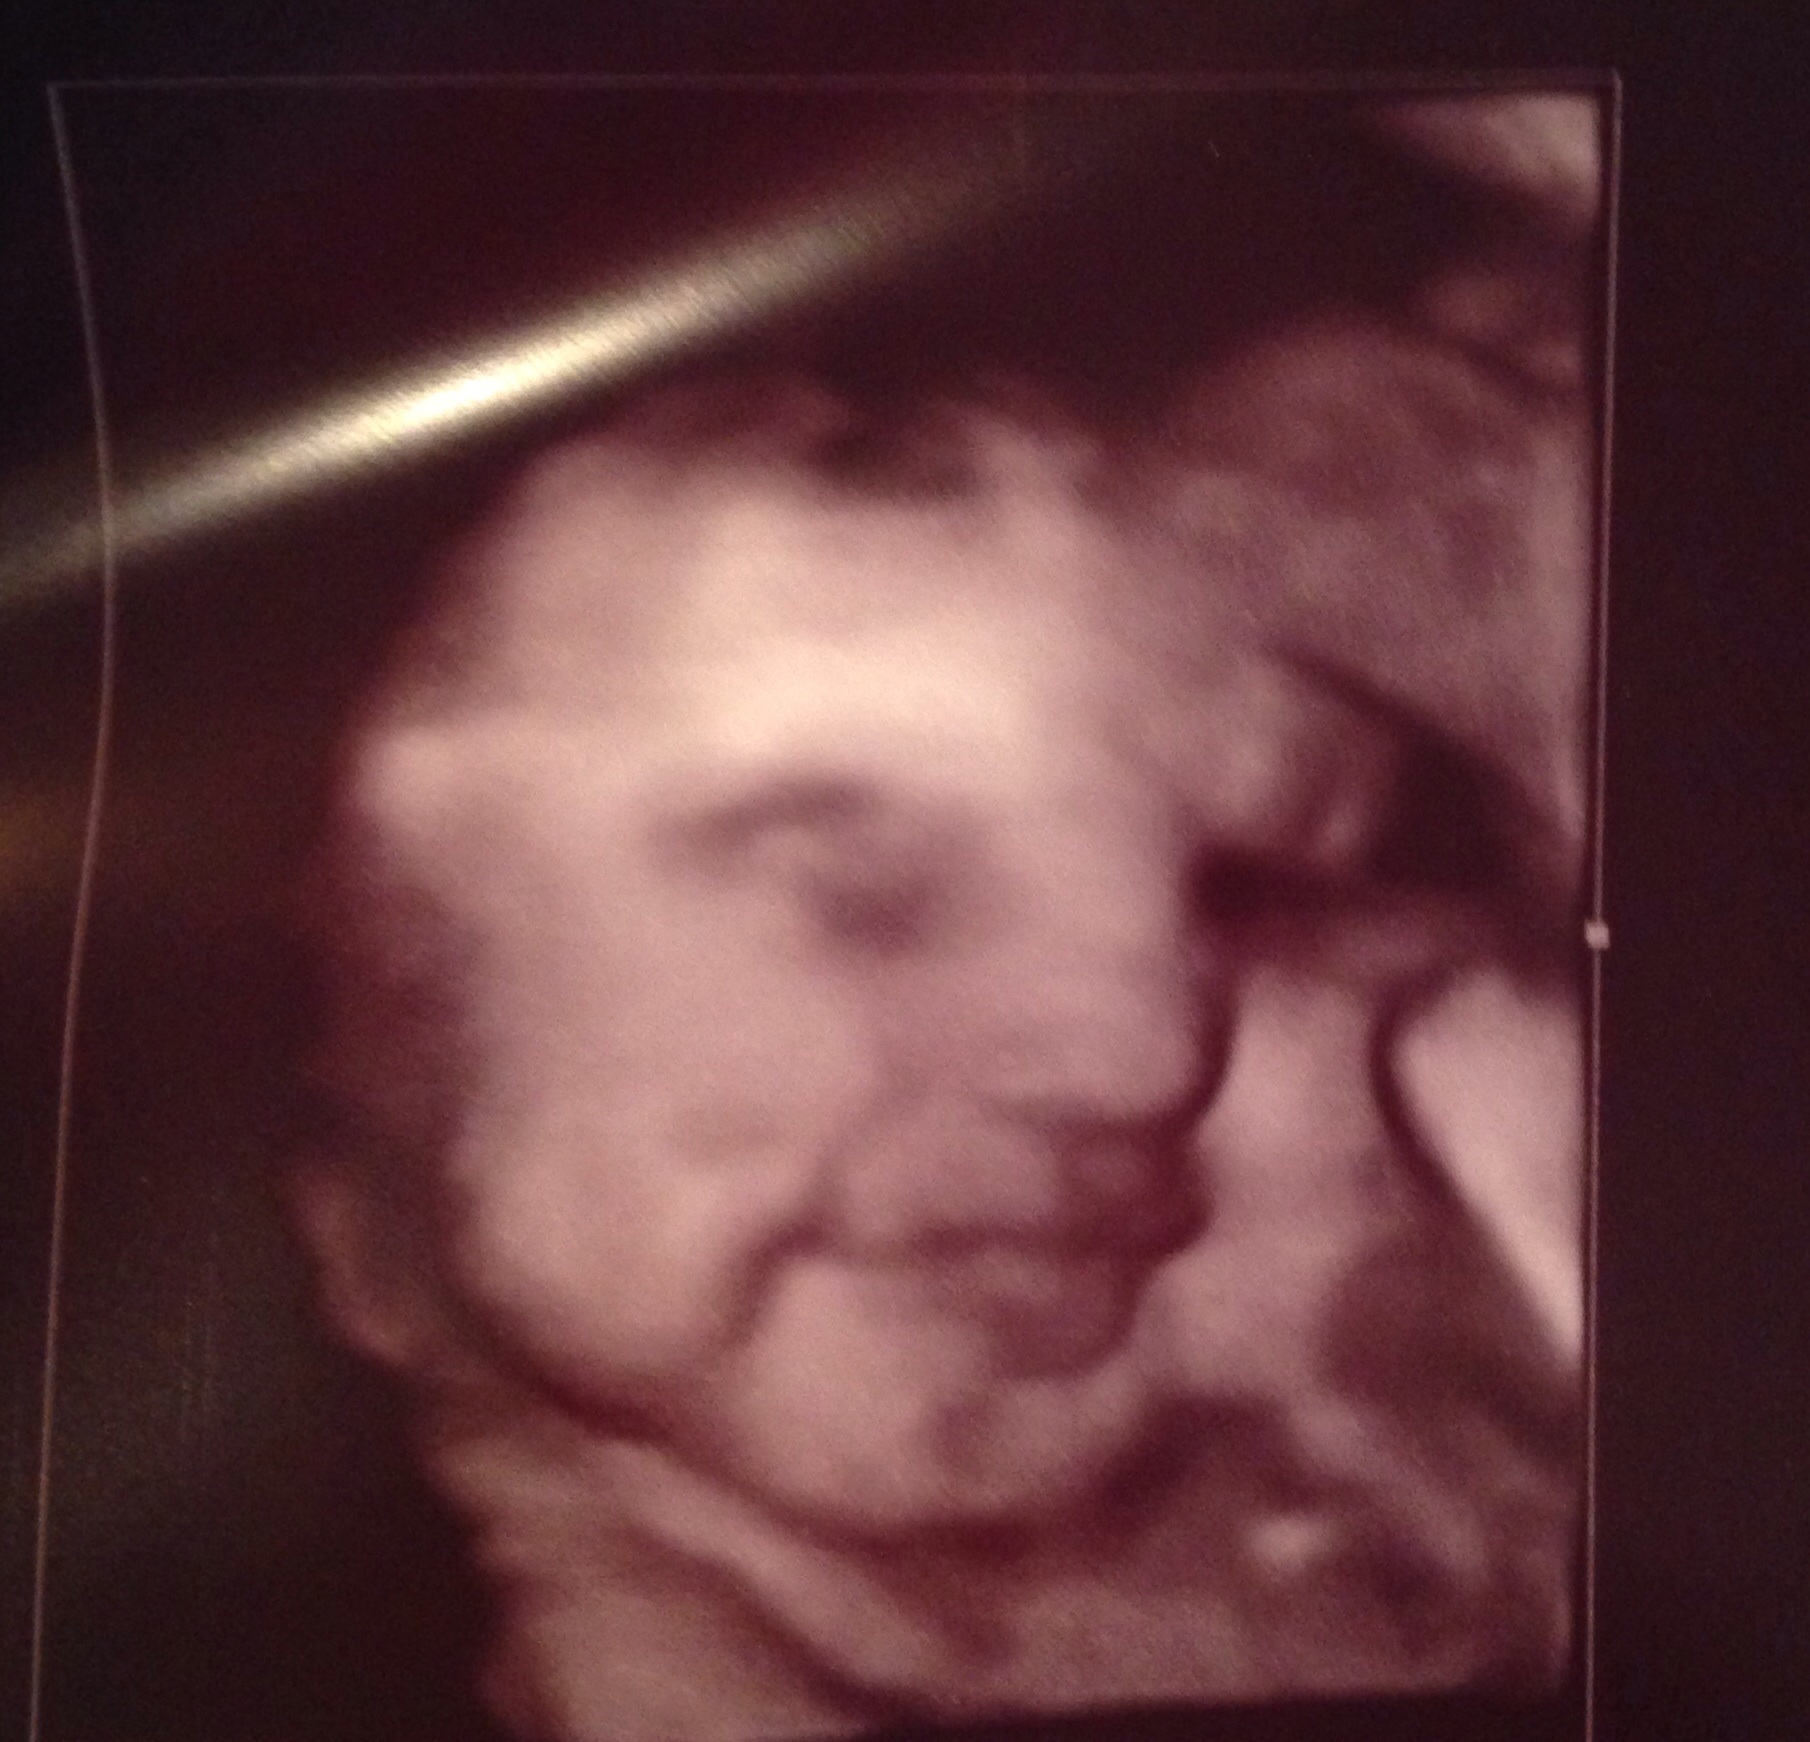

So cute! That's a great pic. @staryb My growth scan took about 20-30 minutes. Most of my u/s are about 20 minutes. Just to give you an idea since it depends on where you go.

Re: Serious AW: growth scan ultra sound